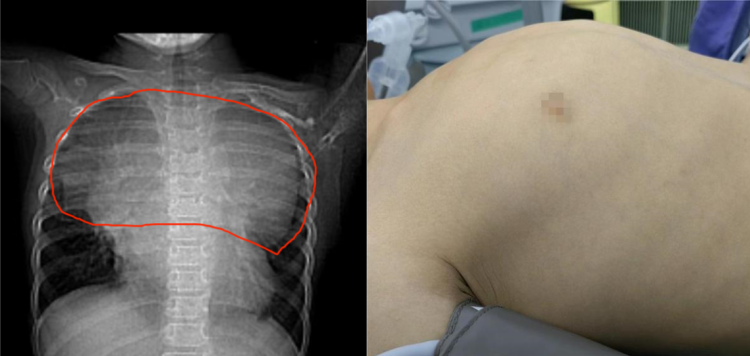

不久前,乐乐的爸爸妈妈发现他胸廓突起很明显,在当地就诊,医生初步怀疑是鸡胸,可继续观察或待手术。可是,乐乐爸爸妈妈心里还是有些疑问,为什么孩子总是这么瘦,怎么吃都长不胖呢? CT检查竟然发现乐乐胸腔里有一个非常大的肿瘤,几乎占据一半的胸腔空间。

新华医院儿心脏中心主任鲁亚南教授是国内小儿心胸外科领域的顶级专家,乐乐入院后迅速完善了胸部增强CT和MRI-,所有人都震惊了,巨大的肿瘤压迫并推挤着心脏、气管和主动脉、腔静脉、肺静脉等大血管,幷造成有明显的气管狭窄和心包积液,病情危在旦夕。

正如术前预料的一样,进入胸腔后,医生首先看到了巨大的肿瘤,且与两侧的肺和深面的心脏粘连,这是预想中最困难的情况,手术风险也是最大的。但手术团队仍然决定在保证安全的前提下,以最快速度分离肿瘤,减少手术创伤对孩子带来的风险。最终,历经5个小时,肿瘤被尽可能地完整切除了,切除的肿瘤标本重量超过1千克。乐乐术后24小时内就脱离了呼吸机,顺利转出监护室至普通病房,经过治疗后,快速康复出院。